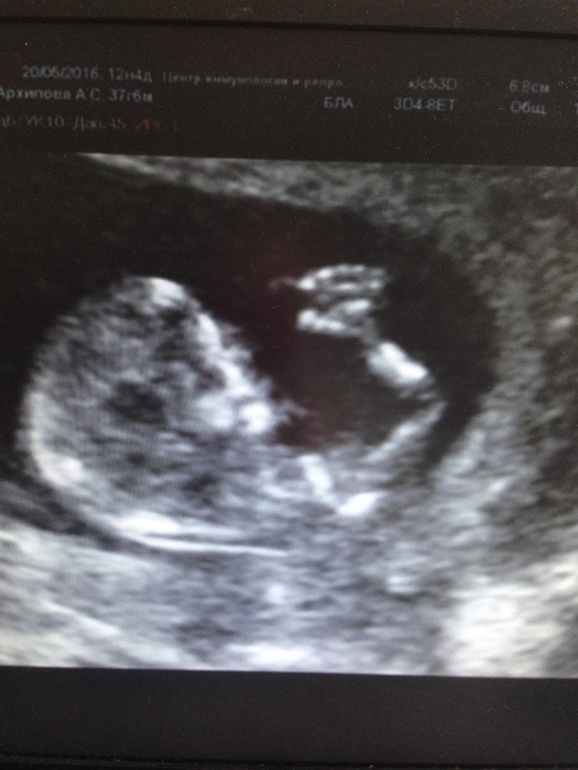

Всем привет малышка машет